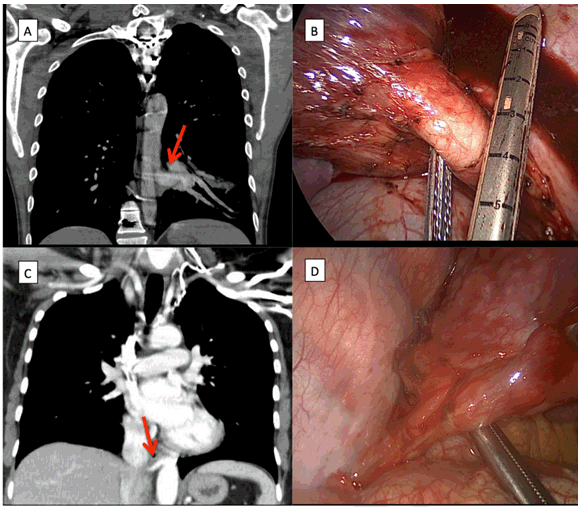

A 29-year-old male presented to the clinic with a 10-year history of hemoptysis that had worsened over the previous three months. Computed tomography (CT) showed a left lower lobe pulmonary sequestration with a 1.5 cm anomalous vessel arising from the thoracic aorta (Figure 1A). Left VATS was performed using a 4 cm utility incision placed in the 4th intercostal space in the mid-axillary line, a 1-cm camera port placed in the 7th intercostal space posterior to posterior axillary line and a 1-cm utility incision was placed in the 7th intercostal space in the mid-axillary line. The aberrant vessel coming off the aorta was isolated (Figure 1B) using electrothermal bipolar tissue sealing system and divided by vascular stapler. Three small branches from pulmonary artery to left lower lobe were identified and divided. The patient's pain was well controlled and he was discharged on postoperative day-3 with resolution of his hemoptysis. At follow-up one month later, he had resolution of hemoptysis.

A 37-year-old female presented to her primary care provider with complaints of dyspnea and coughing that had started during a pregnancy the previous year. She had suffered from severe GERD during pregnancy, which resolved after her child was born, but she continued to have a persistent cough and intermittent low fevers. A CT scan of her chest without IV contrast showed that her right lower lobe had bronchiectasis. A bronchoscopy showed irritation of mucosa and a small pocket of pus in the right lower lobe and the washings were negative for malignancy. After course of levaquin for seven days, repeat CT scan with IV contrast showed right lower lobe intralobar pulmonary sequestration with associated abscess (Figure 1C) supplied by 6 mm branch from descending aorta just superior to the diaphragm. The patient underwent right VATS lower lobectomy. Due to the low location of the anomalous branch from the descending aorta, the posterior axillary line incision placed at the 8th, instead of 7th, intercostal space. The 6 mm anomalous branch from the descending aorta just superior to the diaphragm was isolated and divided (Figure 1D). The culture grew Staphylococcus aureus and patient was treated with Levaquin for five days. Her pain was well controlled and she was discharged on postoperative day-2. At follow-up one month after resection, she had resolution of her cough and low-grade fevers.

Figure 1: Aberrant vessel to pulmonary sequestration (A) A computed tomography image shows a 1.5 cm vessel arising from the descending aorta going into the left lower lobe intralobar pulmonary sequestration, (B) A thoracoscopic image of an aberrant blood vessel arising from the aorta with vascular stapler going around the isolated vessel, (C) A computed tomography image shows a 6 mm vessel arising from descending aorta, and (D) A thoracoscopic image of an aberrant blood vessel in the inferior pulmonary ligament isolated by thoracoscopic instrument.